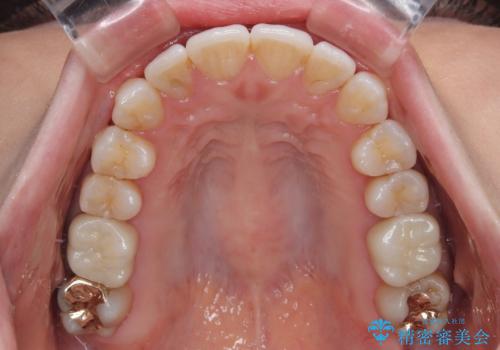

矯正治療後には奥歯の銀歯やむし歯をセラミックやゴールドにて治療を行い、大変整った口腔環境へと改善さ。れました